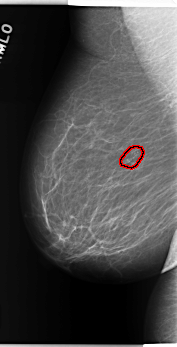

C_0276_1.RIGHT_MLO

RIGHT_MLO LINES 5888 PIXELS_PER_LINE 3000 BITS_PER_PIXEL 12 RESOLUTION 50 OVERLAY

FILE: C_0276_1.RIGHT_MLO.OVERLAY

TOTAL_ABNORMALITIES 1

ABNORMALITY 1

LESION_TYPE CALCIFICATION TYPE PLEOMORPHIC DISTRIBUTION CLUSTERED

ASSESSMENT 4

SUBTLETY 5

PATHOLOGY BENIGN

TOTAL_OUTLINES 1

BOUNDARY